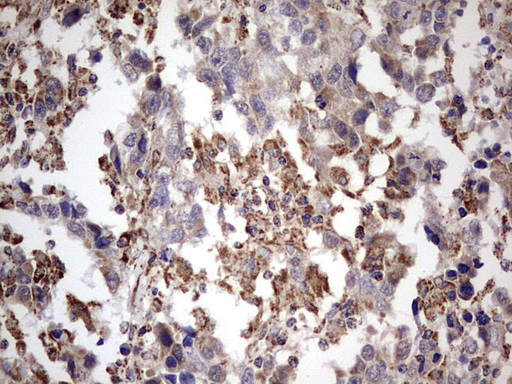

Immunohistochemical staining of paraffin-embedded Adenocarcinoma of Human breast tissue using anti-APC mouse monoclonal antibody. (M00008-2; heat-induced epitope retrieval by 1mM EDTA in 10mM Tris, pH8.5, 120°C for 3min)

Immunohistochemical staining of paraffin-embedded Adenocarcinoma of Human breast tissue using anti-APC mouse monoclonal antibody. (M00008-2; heat-induced epitope retrieval by 1mM EDTA in 10mM Tris, pH8.5, 120°C for 3min)